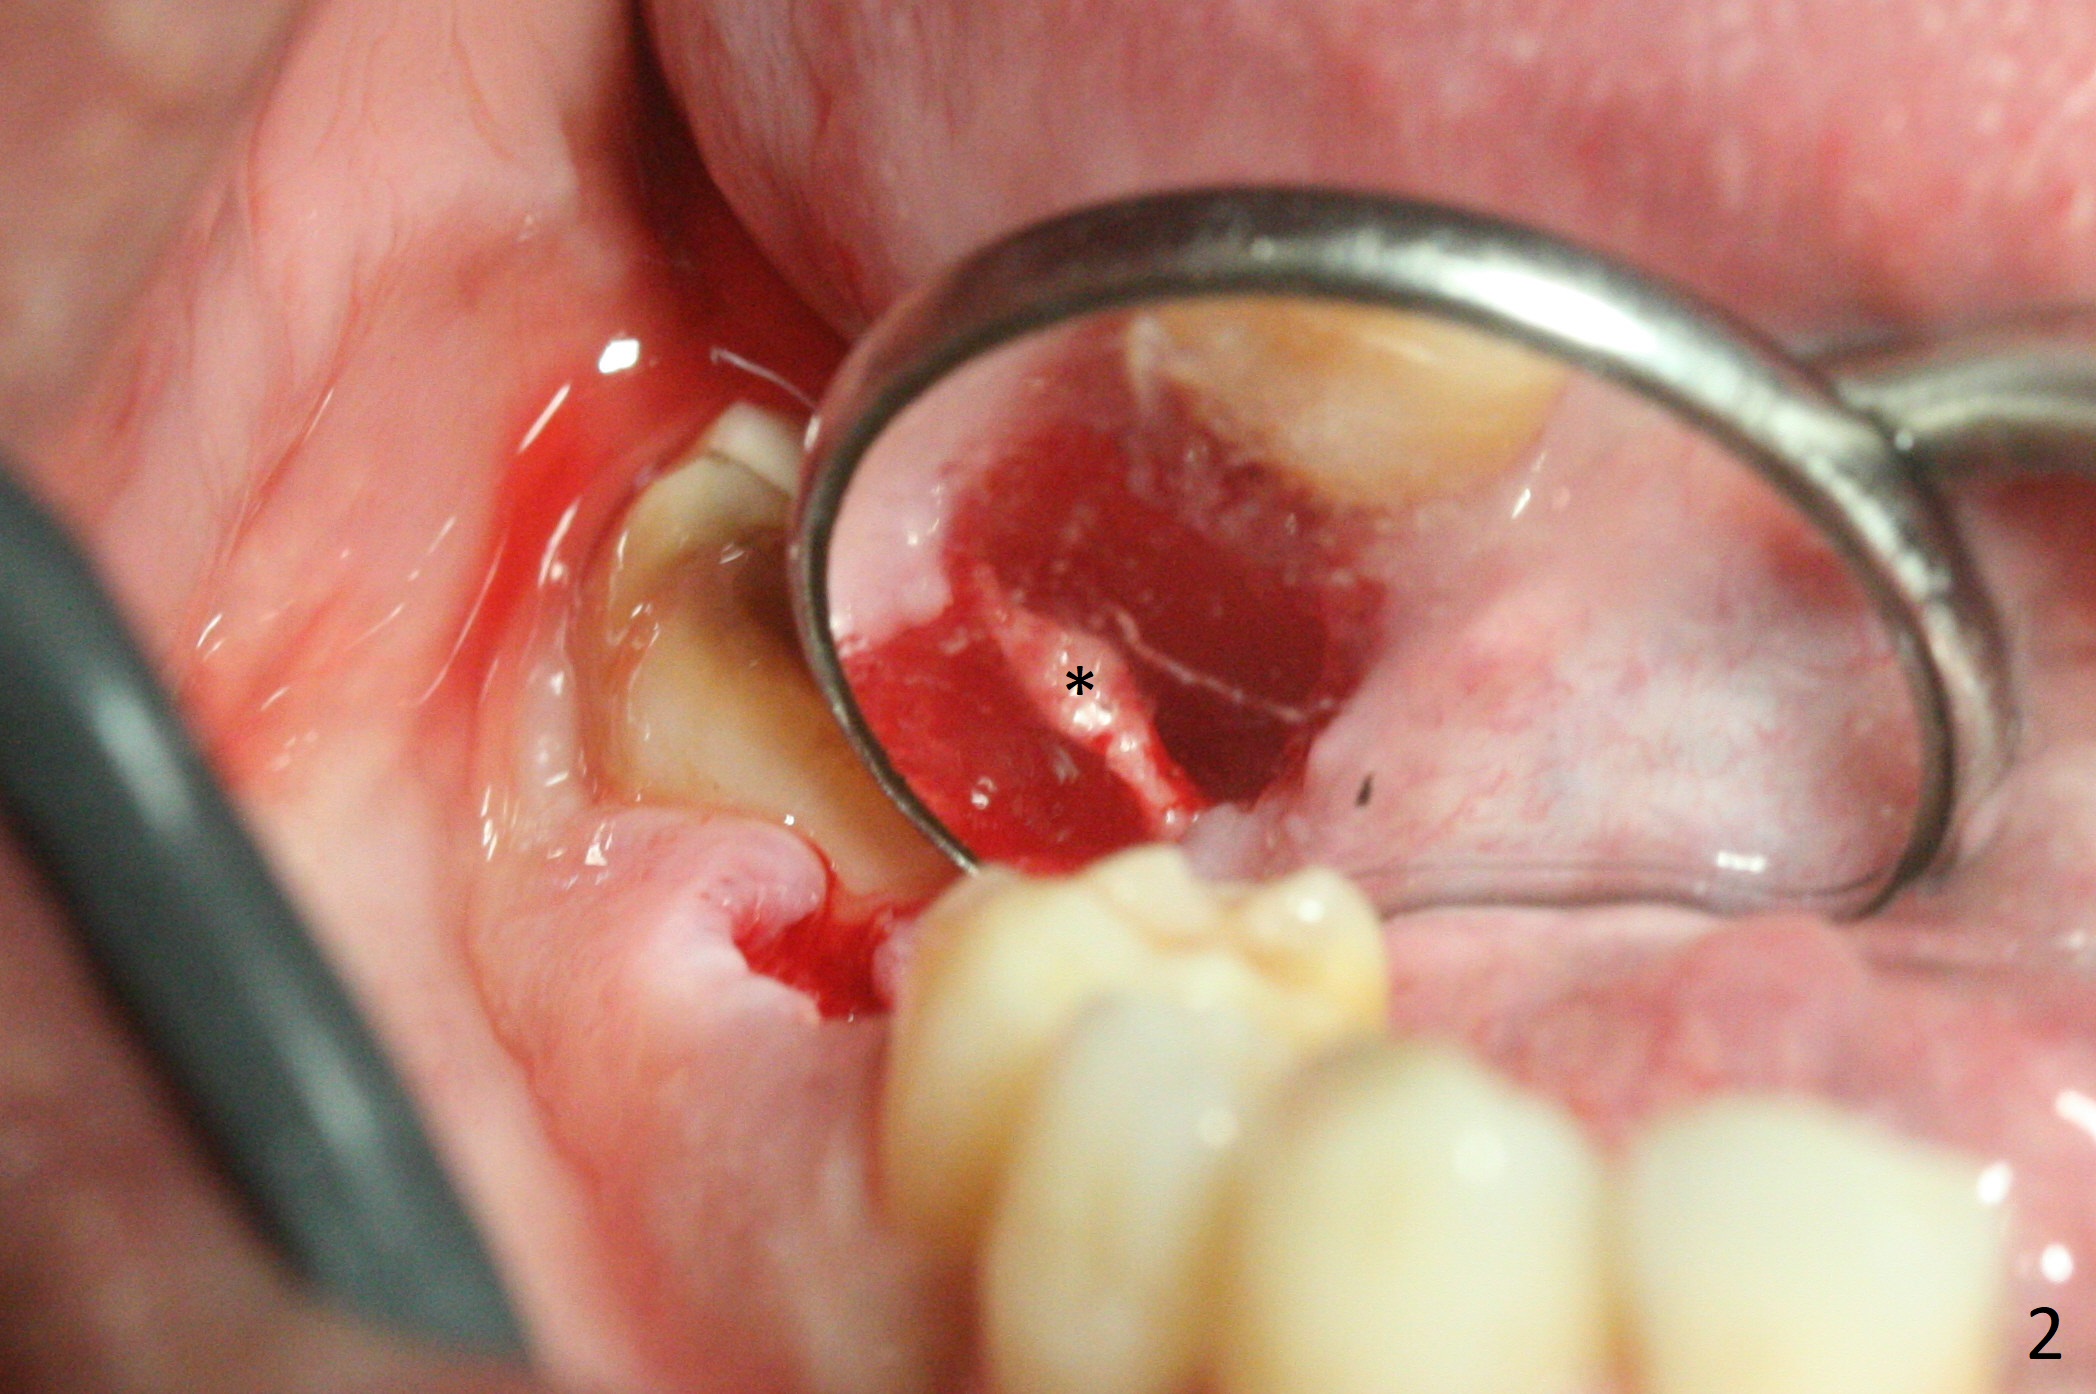

After removal of the residual roots at #30 (Fig.1), a thin septum (Fig.2 *) is removed with Rongeur (Fig.3). Following use of 4.8 mm Magic Drill, a 5x9 mm dummy implant is placed (Fig.4). To reduce socket gap (*), a 6 mm IBS implant is inserted with >50 Ncm (Fig.5). What is unexpected is heavy reduction in the height of a 6.5x4(3) mm abutment (A) because of the short crown height of the lower posterior teeth (Fig.1) and supraeruption of the tooth #3. The immediate provisional is unstable postop. The remade one dislodges soon, so does the abutment (Fig.6, 3 months postop). It appears that bone pattern in the distal socket changes.